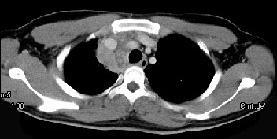

问题 男,21岁,干咳,盗汗一月伴消瘦,CT如图,应先考虑为 ( )

选项 A、右上肺上沟瘤 B、右上肺不张 C、纵隔型肺癌并纵隔淋巴结核转移 D、淋巴瘤 E、右上肺结核并纵隔淋巴结核

答案 E